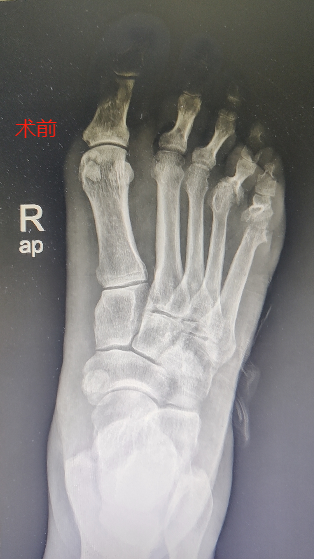

近一年来,她的右足皮肤严重破损、大面积溃烂,不但严重影响了她的行动能力,肢端的疼痛及流脓更是让她倍感痛苦。

经多次对症治疗,效果不佳,最终无奈选择了截肢手术。

尽管已经截肢,但柏女士的糖尿病足伤口愈合仍然困难重重,我院骨科采用了综合治疗方案,其中包括调整降糖方案、改善组织循环和代谢、营养神经、抗炎等治疗手段。经过了一个多月的精心治疗,柏女士的伤口终于愈合了。